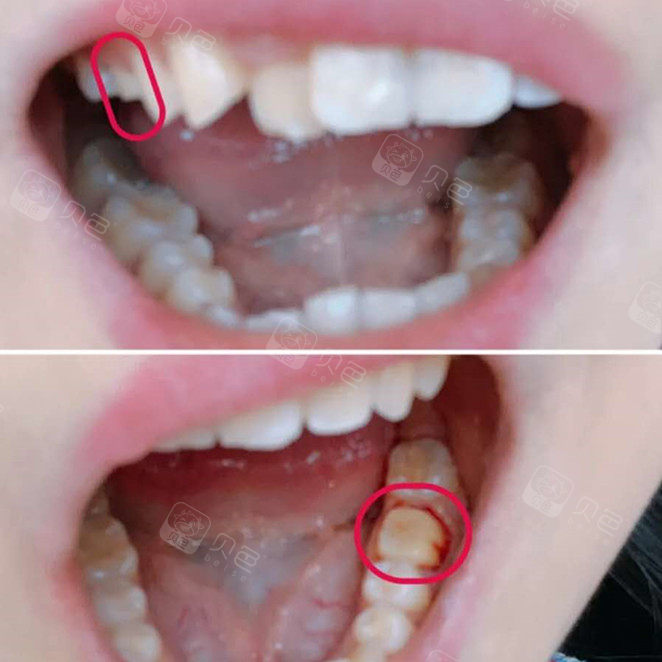

复杂根管治疗残冠根管治疗一例

左上后牙残冠显微根管再修复一例